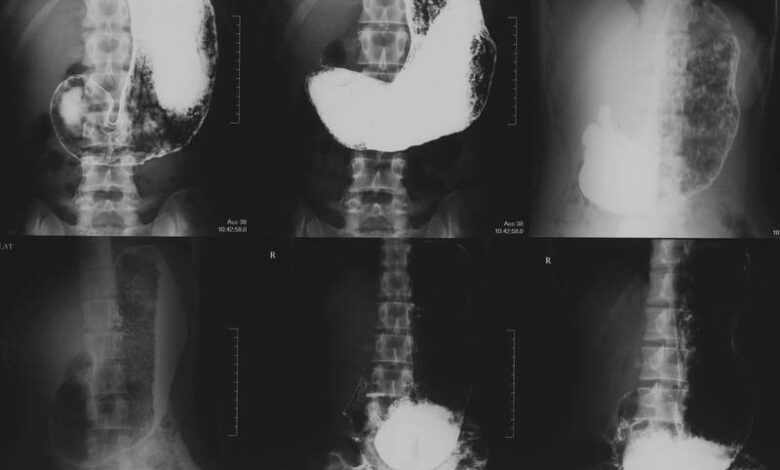

Сама процедура гастроэнтероскопии проводится в специально оборудованной процедурной комнате. Врач вводит гастроскоп через рот пациента, чтобы исследовать пищевод, желудок и начальный отдел тонкого кишечника.